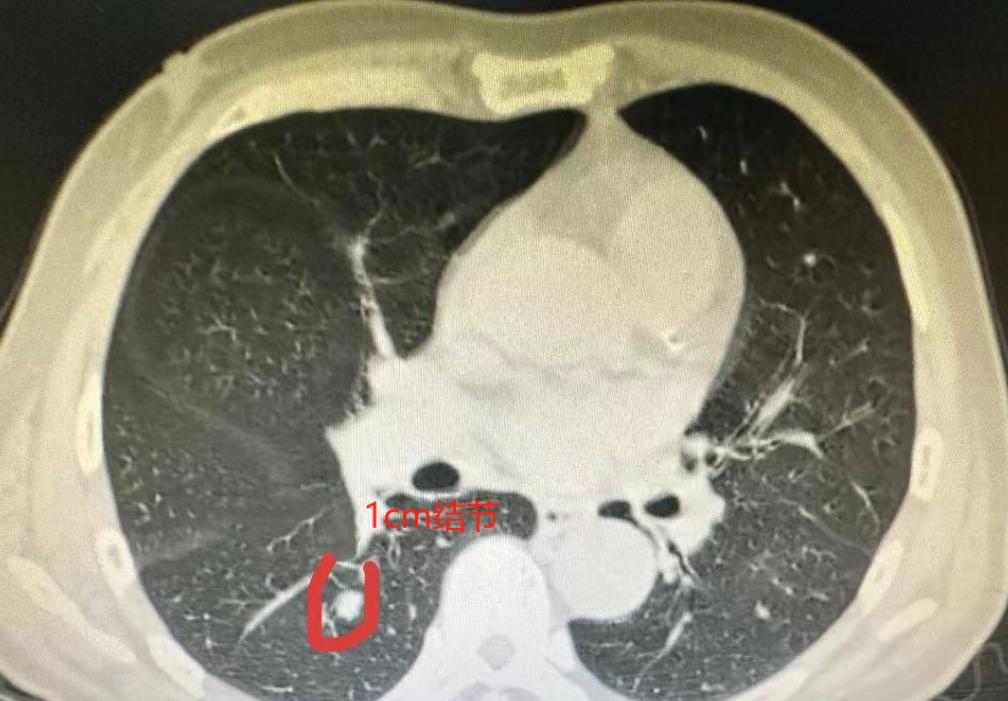

肺多发结节的手术,在我看来,不单是技术活,更像是一门“艺术”!前段时间,有位60